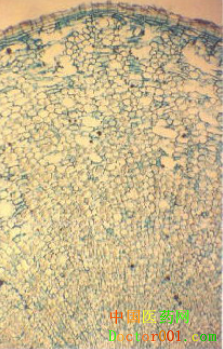

【標題】 五加皮 【拼音】 Wujiapi 【概述】 為五加科植物細柱五加Acanthopanax gracilistylusW.W.Smith的干燥根皮。習稱“南五加皮”。主產于湖北、河南、安徽等地。夏、秋采挖,剝取根皮,曬干。切厚片,生用。 【性味歸經】 辛、苦,溫。歸肝、腎經。 【功效】 祛風濕,補肝腎,強筋骨,利水。 【應用】 1.風濕痹證。本品辛能散風,苦能燥濕,溫能祛寒,且兼補益之功,為強壯性祛風濕藥,尤宜于老人及久病體虛者。治風濕痹證,腰膝疼痛,筋脈拘攣,可單用或配當歸、牛膝、地榆等,如五加皮酒(《本草綱目》);亦可與木瓜、松節同用,如五加皮散(《沈氏尊生書》)。 2.筋骨痿軟,小兒行遲,體虛乏力。本品有溫補之效,能補肝腎,強筋骨。又常用于肝腎不足,筋骨痿軟者,常與杜仲、牛膝等配伍,如五加皮散(《衛生家寶》);治小兒行遲,則與龜甲、牛膝、木瓜等同用,如五加皮散(《保嬰撮要》)。 3.水腫,腳氣。本品能溫腎而除濕利水。治水腫,小便不利,每與茯苓皮、大腹皮、生姜皮、地骨皮配伍,如五皮散(《和劑局方》);若風寒濕壅滯之腳氣腫痛,可與遠志同用,如五加皮丸(《瑞竹堂經驗方》)。 【用法用量】 煎服,4.5~9g;或酒浸、入丸、散服。 【臨床研究】 1.化學成分:本品含丁香苷,刺五加苷B1,右旋芝麻素,16α-羥基-(一)-貝殼松-19-酸,左旋對映貝殼松烯酸,β-谷甾醇,β-谷甾醇葡萄糖苷,硬脂酸,棕櫚酸,亞麻酸,維生素A、B1,揮發油等。 2.藥理作用:五加皮有抗炎、鎮痛、鎮靜作用,能提高血清抗體的濃度、促進單核巨噬細胞的吞噬功能,有抗應激作用,能促進核酸的合成、降低血糖,有性激素樣作用,并能抗腫瘤、抗誘變、抗潰瘍,且有一定的抗排異作用。 【參考文獻】 1.《神農本草經》:“主心腹疝氣腹痛,益氣,療躄,小兒不能行,疽瘡陰蝕。” 2.《名醫別錄》:“主男子陰痿,囊下濕,小便余瀝,女人陰癢及腰脊痛,兩腳疼痹風弱,五緩,虛羸,補中益精,堅筋骨,強志意,久服輕身耐老。” 3.《本草思辨錄》:“五加皮,宜下焦風濕之緩證。若風濕搏于肌膚,則非其所司。古方多浸酒、釀酒及酒調末服之,以行藥勢。” 【附注】 同屬植物作五加皮入藥的尚有:無梗五加 Acanthopanax sessiliflorus (Rupr. et Maxim.) Seem.、紅毛五加 A.giraldii Harms、糙葉五加 A. henryi (Oliv.) Harms、藤五加 A. leucorrhizus (Oliv.) Harms、烏蘞莓五加 A. cissifolius (Griff.) Harms等。 古代所用的五加皮包括五加科五加屬的多種植物,除上述品種外,似亦應包括刺五加Acanthopanax senticosus (Rupr. et Maxim.) Harms在內,而《中國藥典》現已將其作為獨立的藥物收載。現在使用的五加皮藥材,有南五加皮和北五加皮之分。北五加皮為蘿藦科植物杠柳Periploca sepium Bge的根皮(見利水滲濕藥),《中國藥典》以“香加皮”之名收入。南五加皮與北五加皮科屬不同,功效有異,且北五加皮有毒,不應混用。 【圖片】 五加 ![]() 五加皮 ![]() 五加皮植株 ![]() 無梗五加 ![]() 細柱五加 ![]() 藥材五加皮 ![]() 藥材五加皮橫切面 ![]() (責任編輯:Doctor001) |